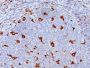

This antibody recognizes a glycoprotein of 110 kDa, which is identified as CD68. It is important for identifying macrophages in tissue sections. It stains macrophages in a wide variety of human tissues, including Kupffer cells and macrophages in the red pulp of the spleen, in lamina propria of the gut, in lung alveoli, and in bone marrow. It reacts with myeloid precursors and peripheral blood granulocytes. It also reacts with plasmacytoid T cells, which are supposed to be of monocyte/macrophage origin. It shows strong granular cytoplasmic staining of chronic and acute myeloid leukemia and also reacts with rare cases of true histiocytic neoplasia. Lymphomas are negative or show few granules.

Tonsil, lymph node, or spleen

IHC, FFPE (verified)

IHC (FFPE) (verified)

Higher concentration may be required for direct detection using primary antibody conjugates than for indirect detection with secondary antibody|Immunofluorescence: 0.5-1 ug/mL|Immunohistology formalin-fixed 0.25-0.5 ug/mL|Staining of formalin-fixed tissues is enhanced by boiling tissue sections in 10 mM citrate buffer, pH 6.0, for 10-20 min followed by cooling at RT for 20 minutes|Flow Cytometry 0.5-1 ug/million cells/0.1 mL|Does not react with pig, dog, or chicken; others not known|Optimal dilution for a specific application should be determined by user